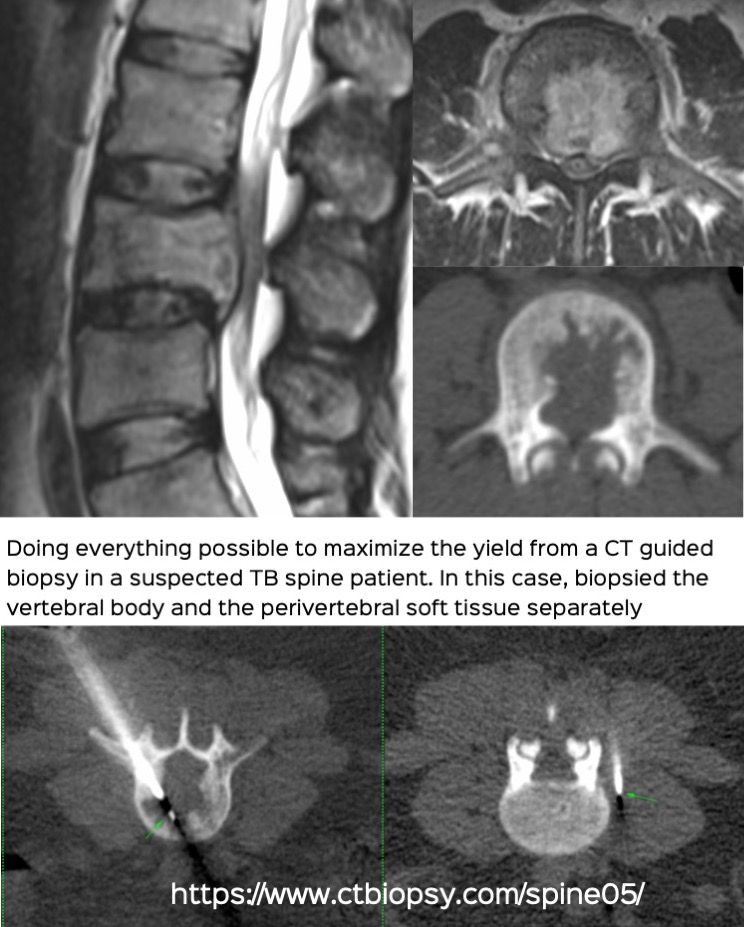

Case 68: How to Maximize Your Yield in a Suspected TB Spine Biopsy

Bhavin Jankharia - 26 November 2021